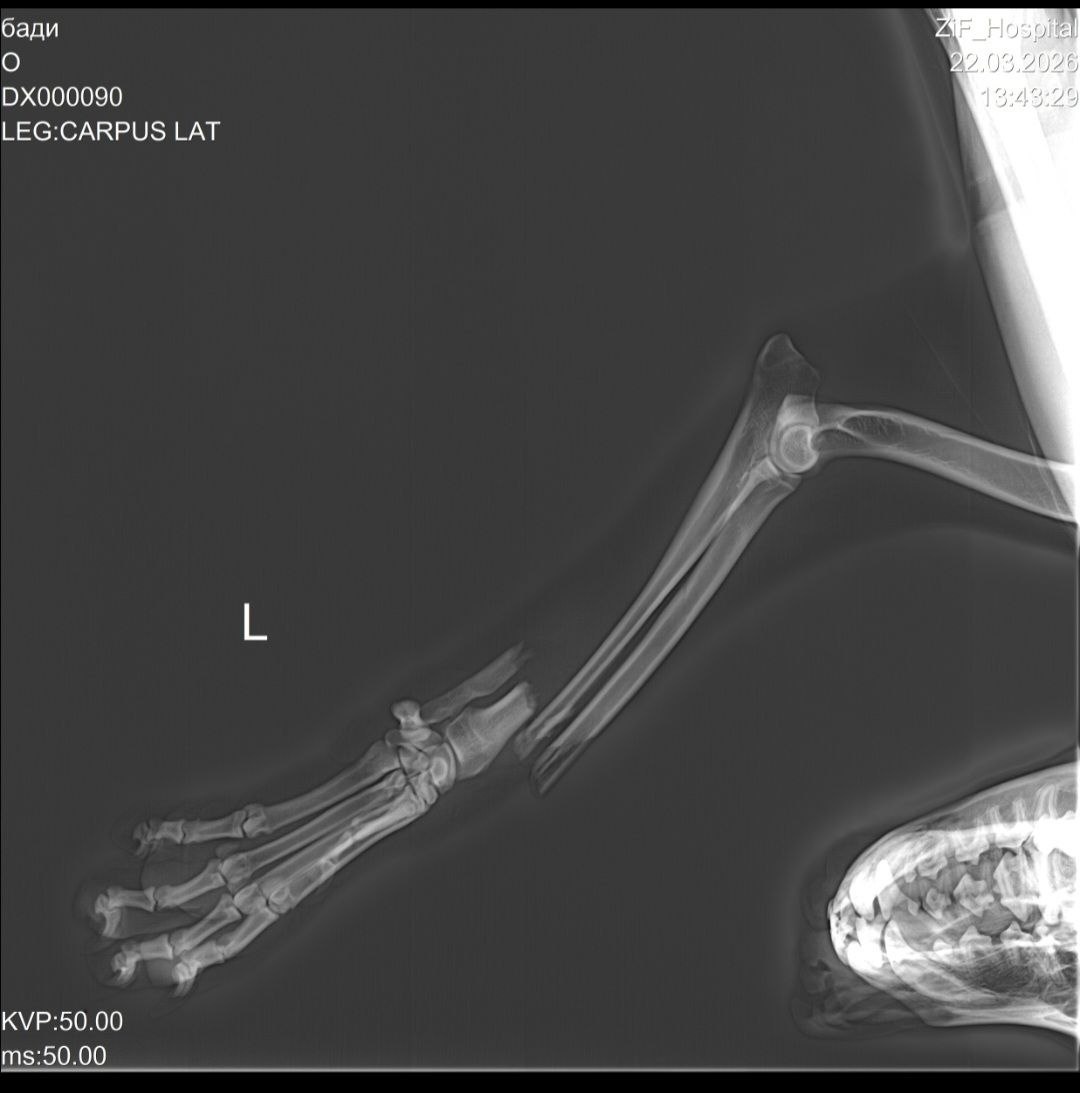

У Бадди открытый перелом . Сломаны две косточки. Из-за того что он лежал с открытой раной долгое время, на лапе начался некроз мягких тканей. От боли пёс даже пытался отгрызть себе лапу.

Если удасться собрать нужную помощь малышу установят внешний фиксатор и спицы ( тк переломы очень сложные )